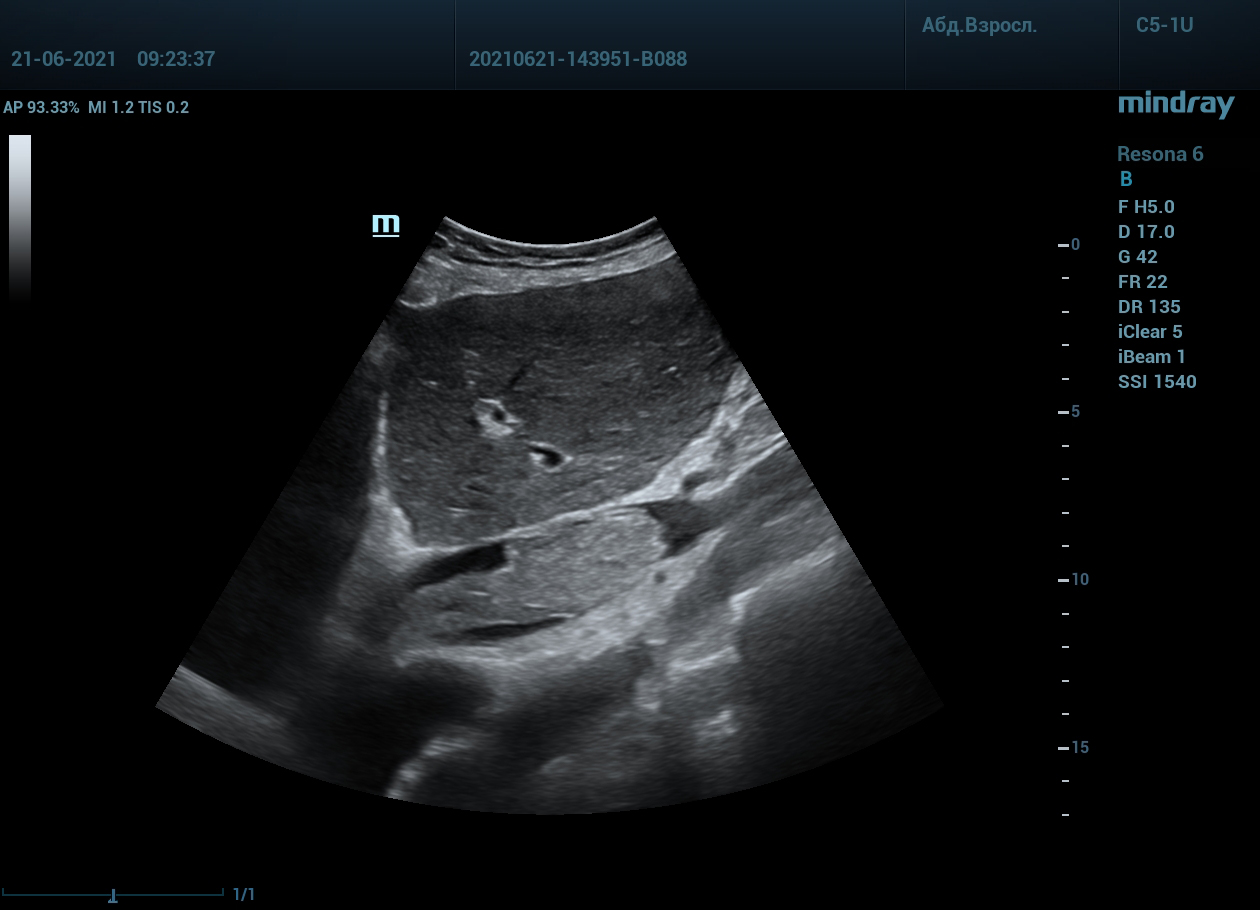

Интересный случай из практики нашего врача-аппликатора. Использовался экспертный ультразвуковой прибор Mindray Resona 6, стандартные заводские пресеты и автоматическая оптимизация iTouch. В эхокардиографии всегда помогает колорайзинг, чаще всего используется оранжевый оттенок. Пациент обследуется перед оперативным лечением по поводу онкологии почки. Вены нижних конечностей у данного пациента без особенностей, сжимаемы и проходимы. Казалось бы, проблема тромбоза миновала но в процессе эхокардиографического исследования, при сканировании нижней полой вены в субкостальном сечении, определяется эхогенное образование. Образование на месте просвета нижней полой вены. Вена расширена, эхогенное включение проникает в правое предсердие. По краю тромба в цветопотоковой визуализации определяется кровоток. Онкологическое заболевание почки осложнилось тромбозом почечной вены, с распространением тромба в нижнюю полую вену и правое предсердие. Изюминку добавляет то, что в других эхокардиографических сечениях тромб совершенно не виден.